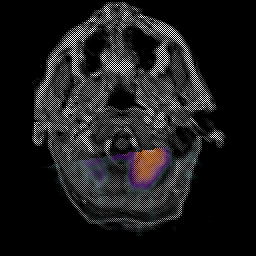

Glioma Overlay -- Slice #1

[Home][Help][Clinical] Slice 1